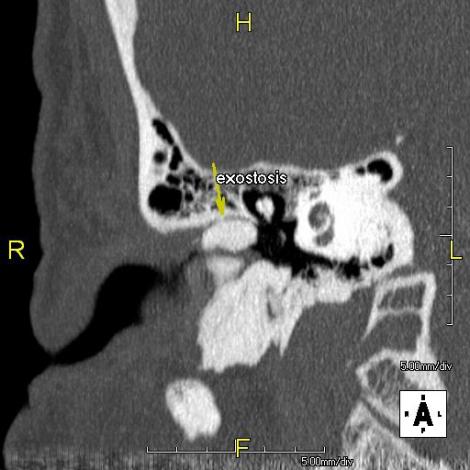

So I took precautions and hoped that I wouldn’t have issues on my IDC/IE. Unfortunately by the Wednesday of the IDC (two days before the IE would begin) my ear because quite seriously infected. So I trudged grudgingly to the doctor. After a quick examination he stated that I was suffering from exostosis. I couldn’t believe that I had that condition. A friend at high school had exostosis in his limbs and had to have many invasive operations to help cure him of it. So what is it? According to Wikipedia:

An exostosis (plural: exostoses) is the formation of new bonw on the surface of a bone. Exostoses can cause chronic pain ranging from mild to debilitatingly severe, depending on the shape, size, and location of the lesion.

Now how does this affect me? Well, I am apparently suffering from a condition known as Surfer’s Ear.

Surfer’s ear is the common name for an exostosis or abnormal bone growth within the ear canal. Surfer’s ear is not the same as swimmer’s ear, although infection can result as a side effect.

Irritation from cold wind and water exposure causes the bone surrounding the ear canal to develop lumps of new bony growth which constrict the ear canal. Where the ear canal is actually blocked by this condition, water and wax can become trapped and give rise to infection. The condition is so named due to its prevalence among cold water surfers. Warm water surfers are also at risk for exostosis due to the evaporative cooling caused by wind and the presence of water in the ear canal.